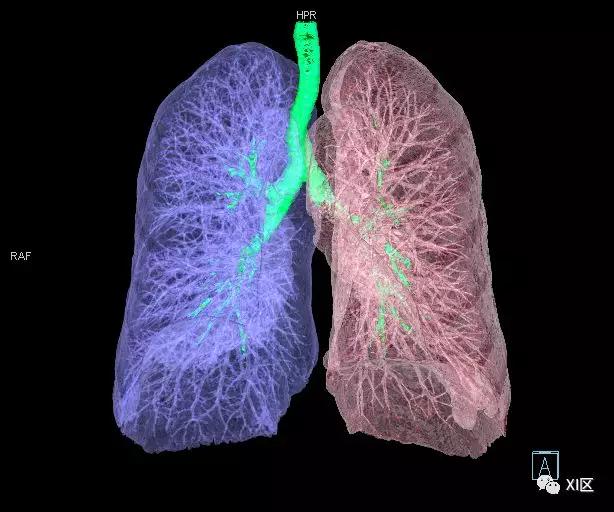

气管支气管树与两肺融合显示

气管树与左右肺的关系

气管树与胸部其他结构的关系